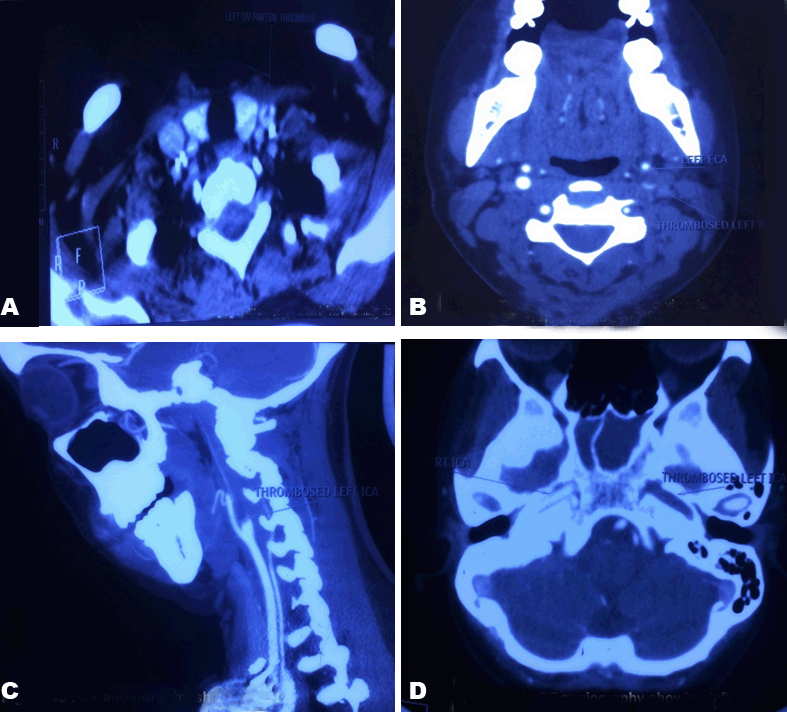

A computed tomography angiography chest (Figure 3) and neck (Figure 4) was done which revealed thrombosed left internal carotid artery (ICA), partially thrombosed left IJV, sphenoid sinusitis and cavitation in bilateral lung fields suggestive of septic emboli. Color doppler bilateral neck was done to assess the extension of thrombus in the vessels. Surprisingly, it showed involvement of both IJV (partially occluded) and ICA (80% occluded) of left side.

Figure 4: (A) Computed tomography angiography showing partial left internal jugular vein thrombosis. (B,C,D) Computed tomography angiography showing left internal carotid artery thrombosis.